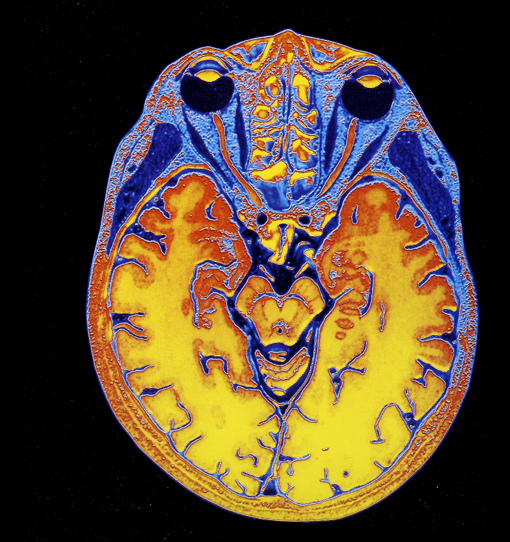

Exposición Cerebro. Viaje al interior. Parque de las Ciencias de Granada. Foto: M. Rodríguez

Escáner cerebral, de Cielo y Tierra (Phaidon)